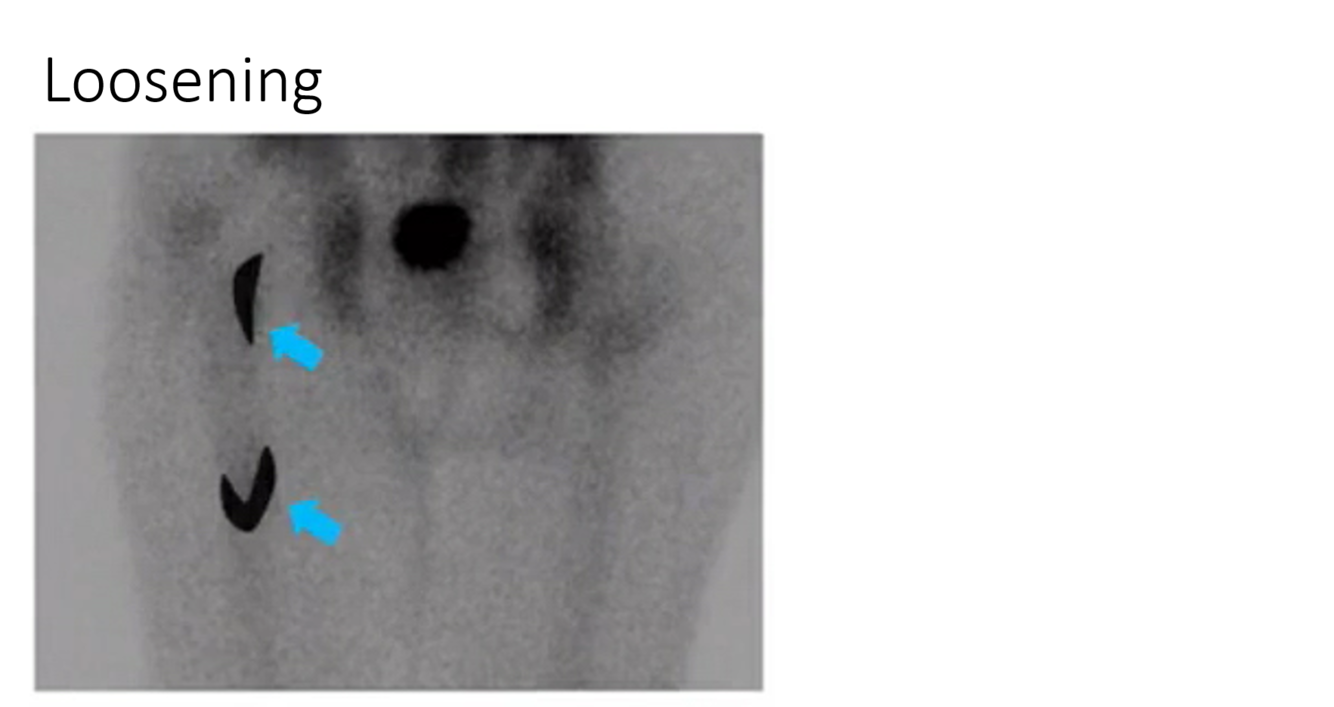

aseptic loosening in a hip prothesis. uptake at wiggle points at the distal part of the femoral component and at the lesser trochanter